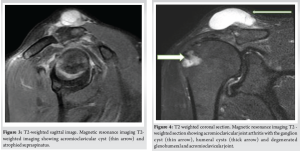

On examination, the shoulder swelling was globular, soft, cystic, fluctuant measuring 3 × 3 cm centered over the AC joint with the overlying skin stretched. There was no anterior joint tenderness or subacromial tenderness. The range of motion was comparable to the opposite side – forward flexion of 160°, abduction of 110° and near-normal internal and external rotations. The movements were associated with crepitus over the AC joint but no pain. Special tests revealed intact, but weak cuff muscles. Plain radiographs revealed superior migration of the humeral head, a sourcil sign of the greater tuberosity, glenohumeral and AC joint arthritis (Fig. 2). The MRI showed synovial thickening, degenerative changes in the AC joint and glenohumeral joint with a hyper-intense homogeneous cystic swelling above the AC joint on T2-weighted imaging (Fig. 3). There was a cut-off geyser sign with no communication to the AC joint or glenohumeral joint (Fig. 4). The supraspinatus was partially intact but atrophied. Considering the patients asymptomatic shoulder, wait and watch approach was considered for a period of 2 months for spontaneous regression. There was no subsidence in the size of the swelling and hence, the patient returned for removal of the lesion.